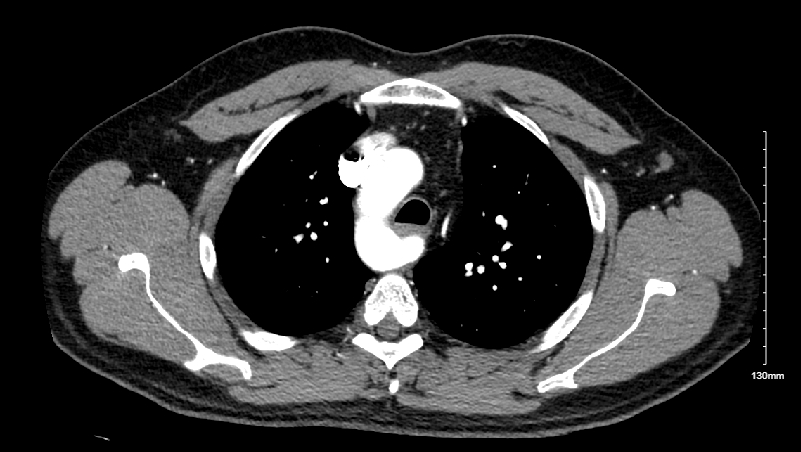

Wrong Turn: Isolated Right-Sided Aortic Arch in the setting of non-ST Elevation Myocardial Infarction

An isolated right-sided aortic arch is a very rare vascular anomaly that usually goes undiagnosed unless symptomatic at birth or during imaging during hospitalization. Here, we present a relatively young patient with a non-ST elevation myocardial infarction (NSTEMI) that was found incidentally to have a right-sided aortic arch.

A 40-year-old male with a past medical history of hypertension, smoking, previous myocardial infarction for which no percutaneous coronary intervention (PCI) was done who presented to the emergency room with left sided chest pain. Initial electrocardiogram (ECG) revealed normal sinus rhythm and a high sensitivity troponin test on admission at hour 0 was negative. A computed tomography scan with intravenous contrast was done, revealing an incidental isolated right-sided aortic arch and an accessory left renal artery. A repeat troponin 12 hours from the first one revealed a value of 1076. Repeat ECG was done which showed nonspecific T wave changes. The patient was loaded with 300 mg of aspirin, 180 mg of ticagrelor, 60 mg of atorvastatin, 0.4 mg of sublingual nitroglycerin, and started on a heparin drip. Decision was made to admit the patient to the cardiac care unit (CCU) for emergent cardiac catheterization. PCI was done on the 15th hour which revealed a 95% stenosis of the distal left circumflex artery and a 70% stenosis of the distal left anterior descending coronary arteries. Angioplasty of the left distal circumflex was performed and a drug-eluting stent was placed with 0% residual stenosis post intervention. Post catheterization, troponins peaked at 1455 at hour 19 and then decreased, with the next value at 898 at the 27th hour. The patient was managed in the CCU and then discharged with outpatient cardiology follow-up.

Congenital large vessel abnormalities are a rare phenomenon and their mechanical impact on vascular diseases are not well established. Right-sided aortic arches are very rare abnormalities and it is possible that this can accelerate shear stress on the endothelial surfaces of the coronary arteries. More studies are needed to elucidate if extra mechanical shear stress could contribute to accelerated atherosclerosis of arteries. Relatively very young patients who present with acute coronary syndrome can be evaluated for congenital vascular structural abnormalities among other causes.